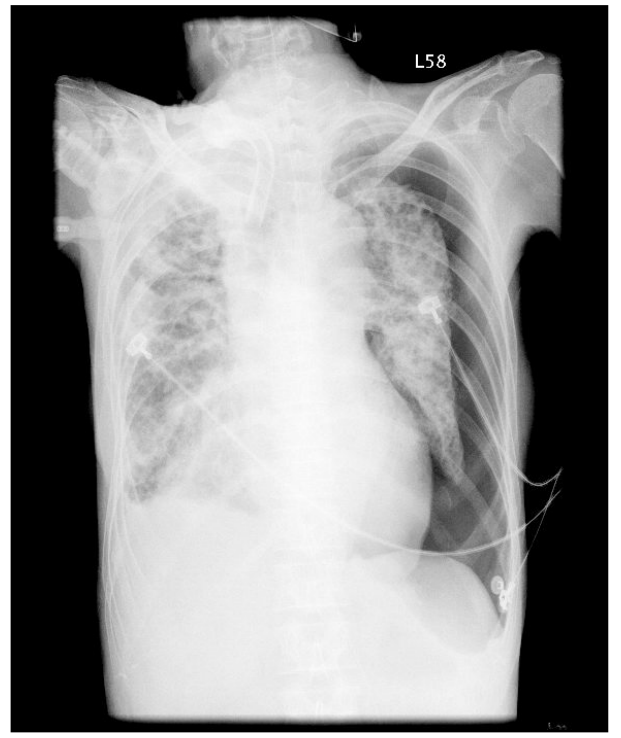

53.出血性休克病人放置中心靜脈導管大量輸血後血壓逐漸回穩。一天後病人發生呼吸困難和血壓下降,聽診發 現右側呼吸音消失。胸部X光片如下,導致病人狀況改變的原因為何? (A)氣管內管阻塞 (B)大量內出血 (C)氣胸 (D)呼吸器相關性肺炎